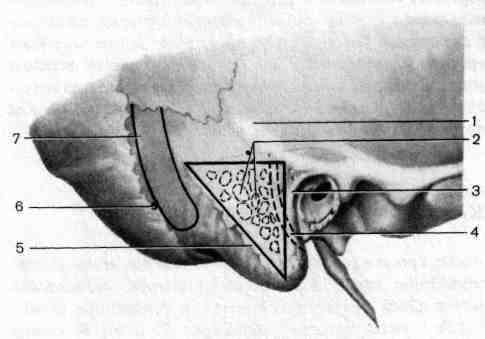

Анатомия сосцевидного отростка